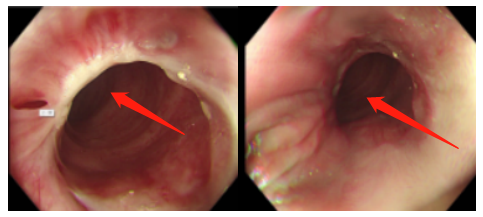

肠镜所见ESD 术后疤痕

一番波折后总算入院,安排术前各项检查。电子结肠镜检查直肠ESD术后齿状线上约1cm可见吻合口,吻合口粘膜光滑完整。MRI影像:直肠癌ESD术后,直肠上段局部肠壁信号异常。